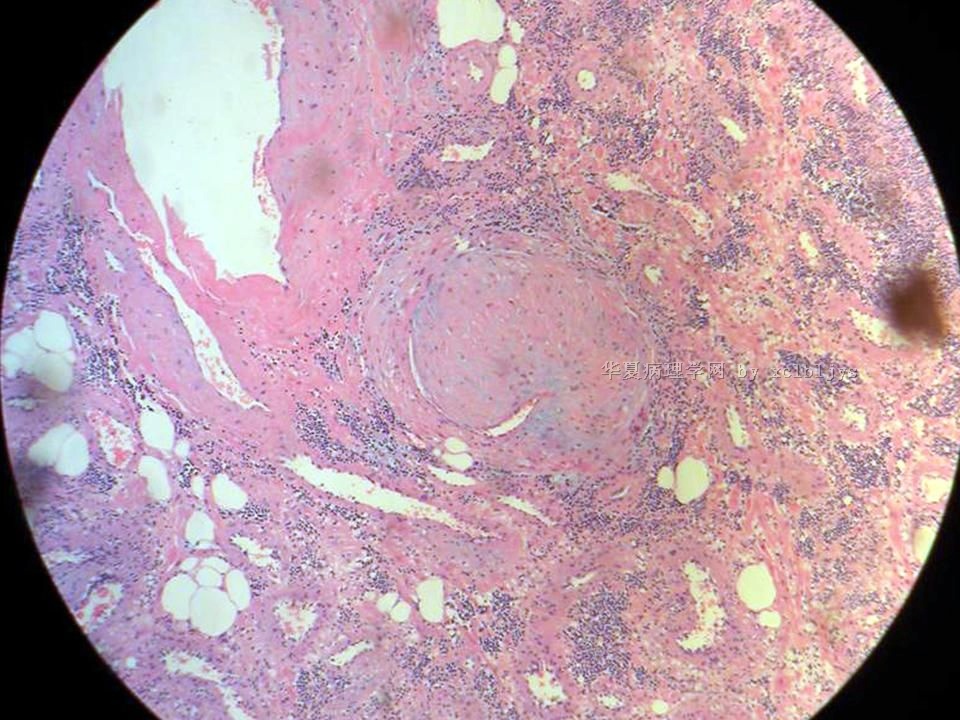

| 以下是引用xclbljys在2010-12-22 17:20:00的发言: 本例我们科室医生有两种意见:一种是炎性假瘤;第二种意见是炎性假瘤伴局限性Wegener肉芽肿。 依据是眼眶内肿块含有大量的动脉内膜炎改变,浸润的炎细胞有淋巴细胞、浆细胞、嗜中性粒细胞和嗜酸细胞等,如图16所示,炎细胞已经浸润动脉壁全层,应符合坏死性小动脉炎,但尚不能确定动脉壁弹力纤维层的破坏。 请各位老师点评! Wegener肉芽肿多发生在上呼吸道、肺、肾脏和皮肤等器官与组织。坏死性血管炎需证实有纤维素样坏死。小动脉炎多在皮肤病变比较明显。本例的小动脉炎或许是炎症引起的继发性改变。需要完善病史,查血免疫指标,看有没有系统性疾病。如果没有系统性疾病,还是考虑慢性炎症继发小血管炎。

血管炎是正常营养/供给血管的炎症性病变,而不是增生血管的炎症。血管炎往往有明显的临床相应症状,如皮疹。典型的Wegerner肉芽肿病有三联症(上呼吸道、肺、肾脏病变)。血管炎不仅是有炎症细胞,同时有血管壁的变性、坏死(纤维素样), 内皮细胞的变质和增生,炎症细胞浸润(包括中性粒细胞、淋巴细胞、组织细胞、嗜酸性细胞、巨细胞等)。不同类型的血管炎累及的血管大小、炎症细胞的类型、有无肉芽肿改变都不相同。血管炎的病因可以是过敏、自身免疫、胶原性疾病、感染等多种因素。